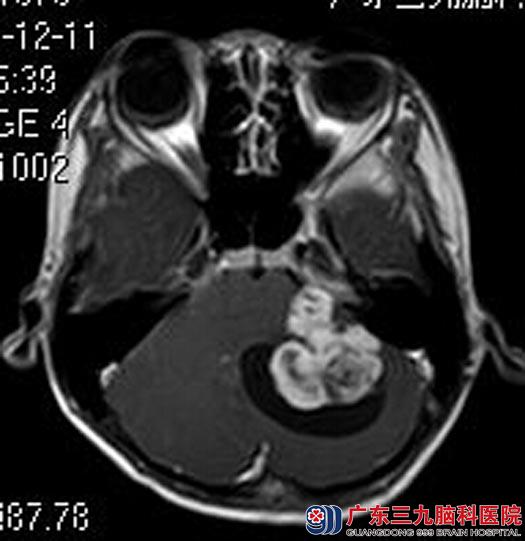

得知是脑瘤,小豪的父母不敢耽误,带着他来到广东三九脑科医院综合神经外科。进一步头颅MR检查:左侧桥小脑角区示囊实性占位病变,大小约32.3mm×39.3mm×33.6mm,考虑脑膜瘤可能性大。

由鲁明主任主刀,在全麻下行左侧桥小脑角区肿瘤切除术,术中显微镜下见肿瘤位于左侧桥小脑角,质软,灰白色,血供少,予镜下全切,中后组颅神经保留完好,术后小豪未再出现呕吐等类似“胃炎”症状,已康复出院。术后病理结果:非典型性脑膜瘤(WHO II级)。